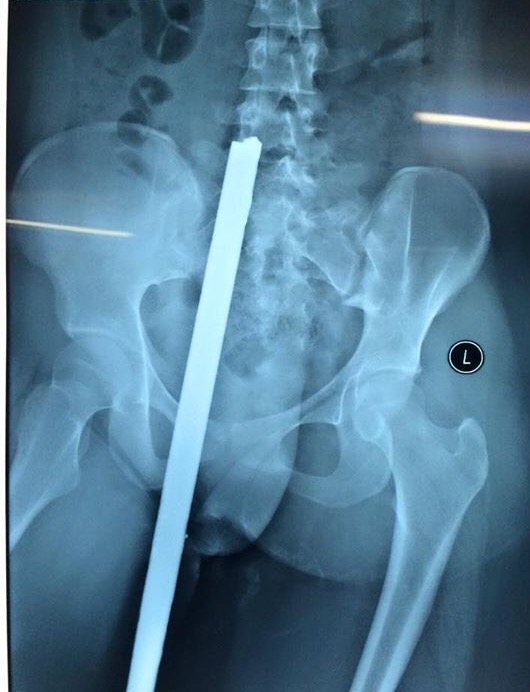

Bệnh nhân nhập viện với thanh sắt (loại thường dùng để làm cốp pha cho các công trình xây dựng) cắm sâu vào trong người. Kết quả chụp X-quang cho thấy thanh sắt dài khoảng 40 cm đâm từ phía sau, dưới mông xuyên đến tận thắt lưng.

Theo thông tin ban đầu từ người thân của nữ sinh này, trên đường đi học về, nữ sinh đang đi xe đạp thì bất ngờ bị thanh sắt dài từ xe 3 bánh chở vật liệu xây dựng đâm phải. Cú đâm mạnh khiến thanh sắt chọc sâu vào cơ thể nữ sinh này. Sau tai nạn, những người xung quanh đã phải dùng máy cưa để cưa đứt thanh sắt dài, sau đó đưa nữ sinh với dị vật đến thẳng BV Việt Đức trong tư thế nằm sấp.

Tại đây, bệnh nhân nhanh chóng được làm các xét nghiệm, chụp chiếu cần thiết sau đó được chuyển thẳng tới phòng mổ. Sau ca phẫu thuật, các y bác sĩ đã rút được thanh sắt ra khỏi cơ thể nạn nhân. May mắn thanh sắt chỉ đâm vào phần mềm, không ảnh hưởng đến xương và thần kinh nên sau ca phẫu thuật, tối cùng ngày, sức khỏe bệnh nhân đã ổn định hơn và tiếp tục được theo dõi.